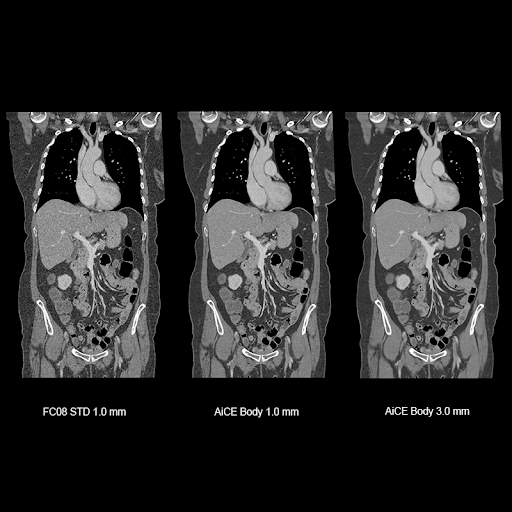

Визуализация органов грудной полости, живота и малого таза